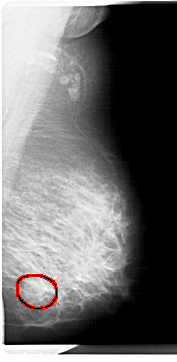

A_1298_1.LEFT_MLO

FILE: A_1298_1.RIGHT_MLO.OVERLAY

TOTAL_ABNORMALITIES 1

ABNORMALITY 1

LESION_TYPE MASS SHAPE ROUND MARGINS OBSCURED

ASSESSMENT 4

SUBTLETY 3

PATHOLOGY BENIGN

TOTAL_OUTLINES 1

BOUNDARY